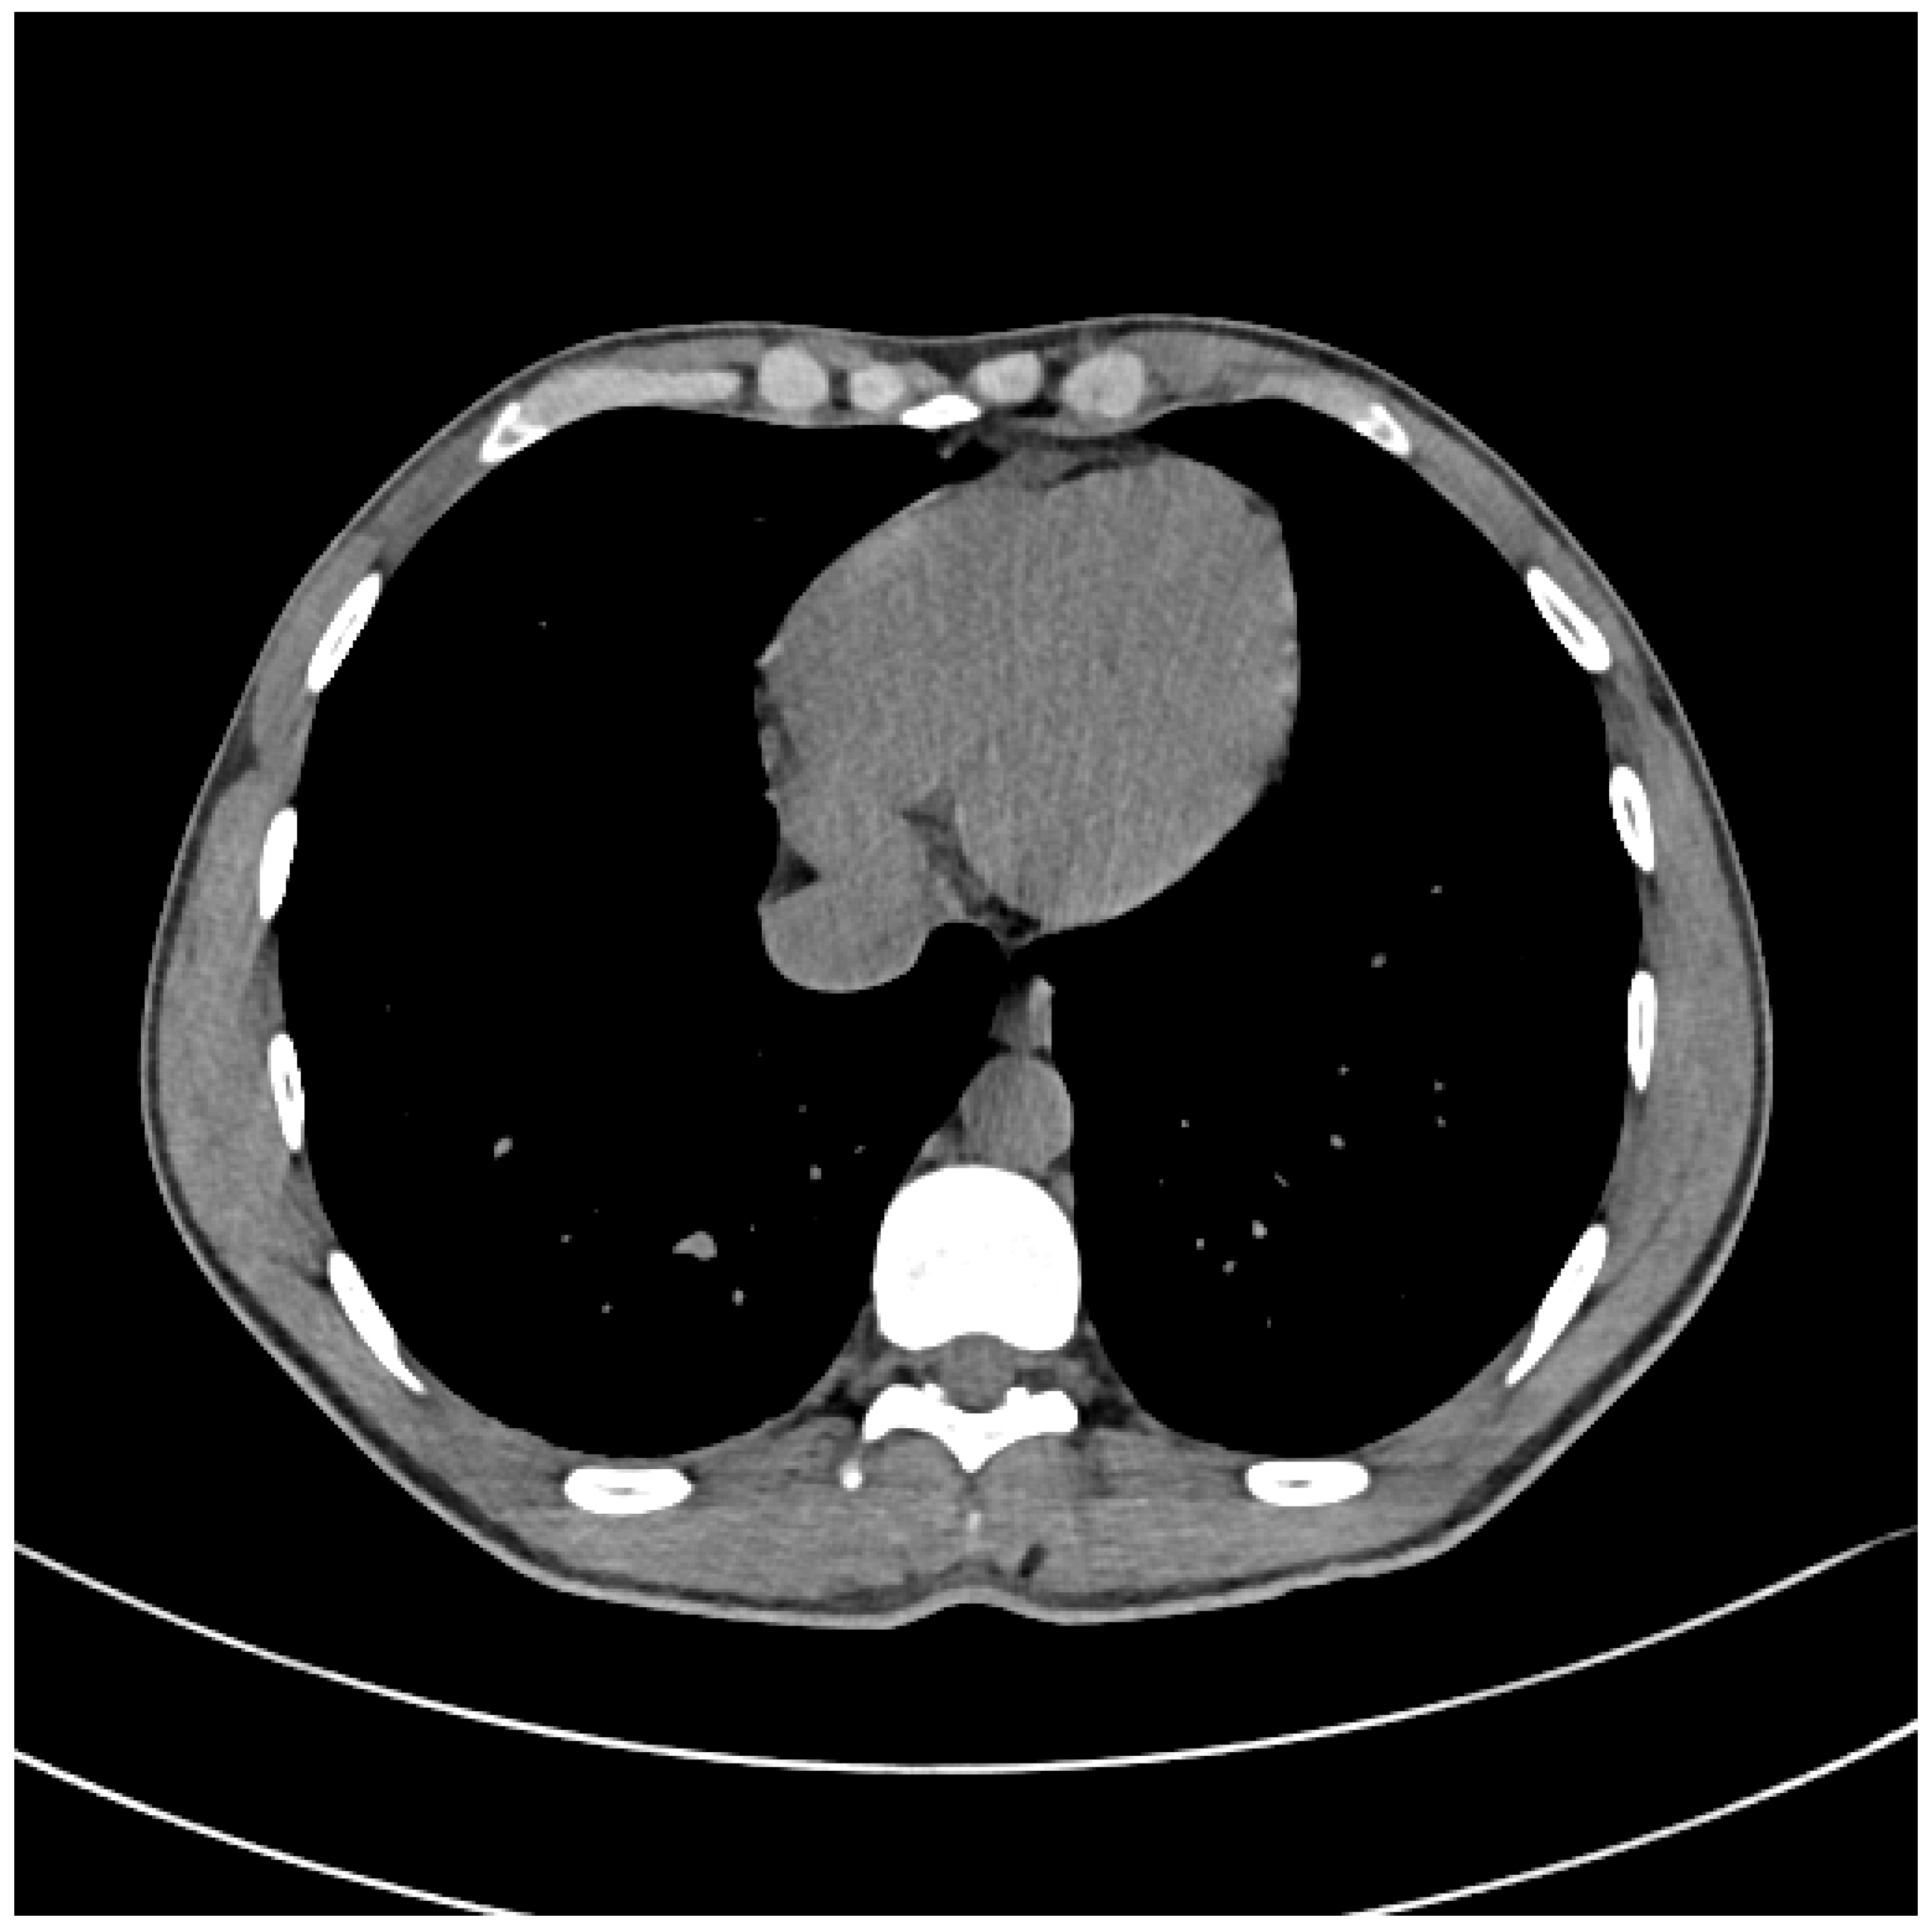

Due to a sudden worsening of the lesion to the lower limb, that was progressively involving the genital region, the patient also underwent a thigh and pelvis CT scan, which was negative for underlying infections, and a chest CT scan, resulting in a positive observation of an air bubble of a diameter of about 5 cm in the right ventricle (Figure 1a,b). For this reason, the patient was sent to our Hyperbaric Unit.

Figure 1.

(a) Pre-HBO: Chest CT scan w/o contrast medium and (b) with contrast medium.